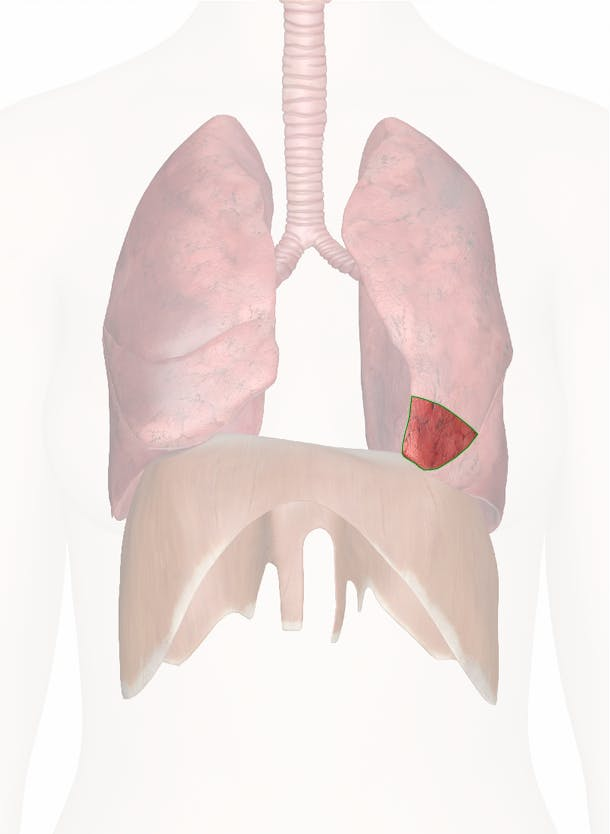

diaphragm

knowt flashcard image

apex of the lungs

base of the lungs

bottom ring of lungs

35

New cards